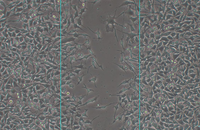

- Investigation of cancer cell migration using Transwell